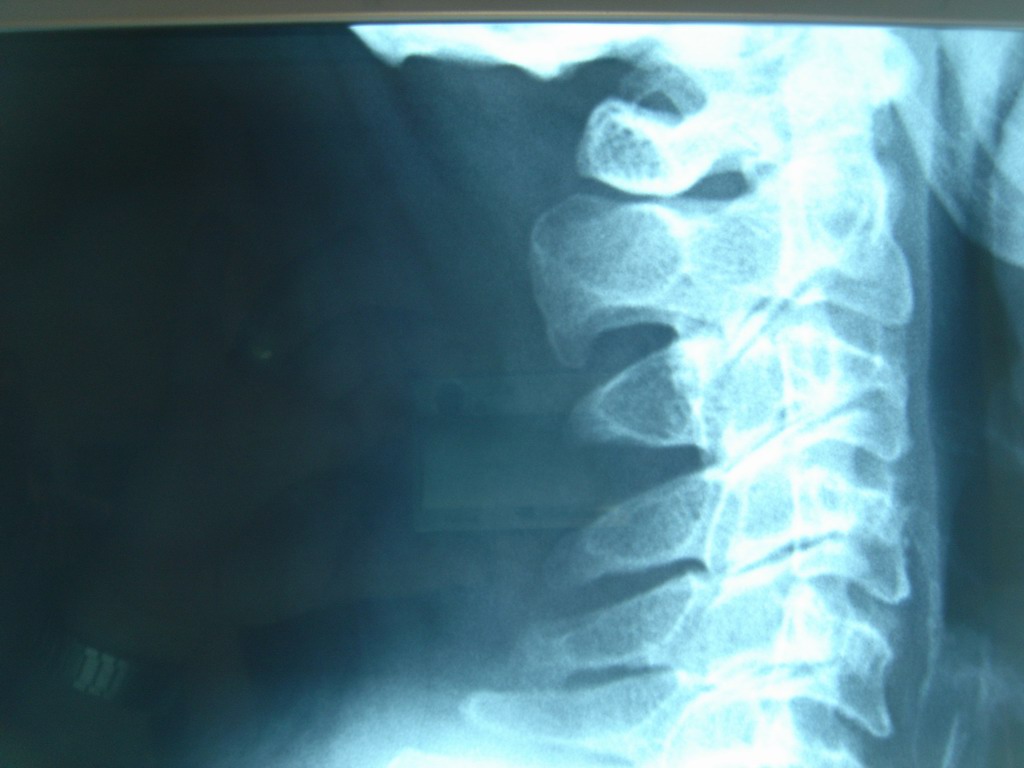

En las radiografías se advierten cambios degenerativos consecutivos a su edad y los repetidos traumatismos que sufren los toreros tanto en su mantenimiento físico como en los accidentes del ruedo.

Obsérvese el desalineamiento de las apófisis espinosas, los osteofitos, etc.

Se pide estudio por Resonancia magnética de cuello y citamos al diestro ya retirado para revisión.

Diagnóstico.  Artrosis cervical